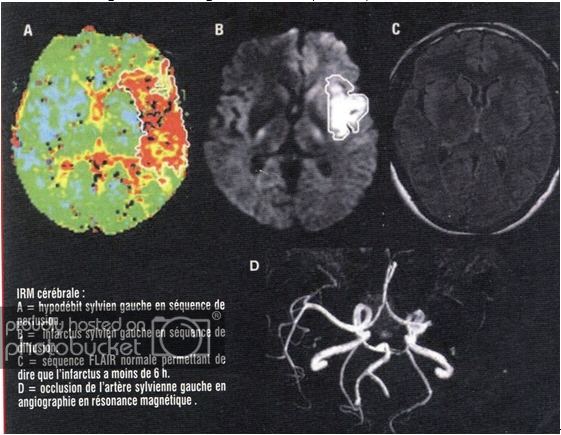

Default TAI BIẾN MẠCH MÁU NÃO

TAI BIẾN MẠCH MÁU NÃO

( ACCIDENT VASCULAIRE CÉRÉBRAL)

JEAN-LOUIS VINCENT, Chef du Service de soins intensifs , Hôpital Erasme, Bruxelles.

Bác Sĩ Nguyễn Văn Thịnh